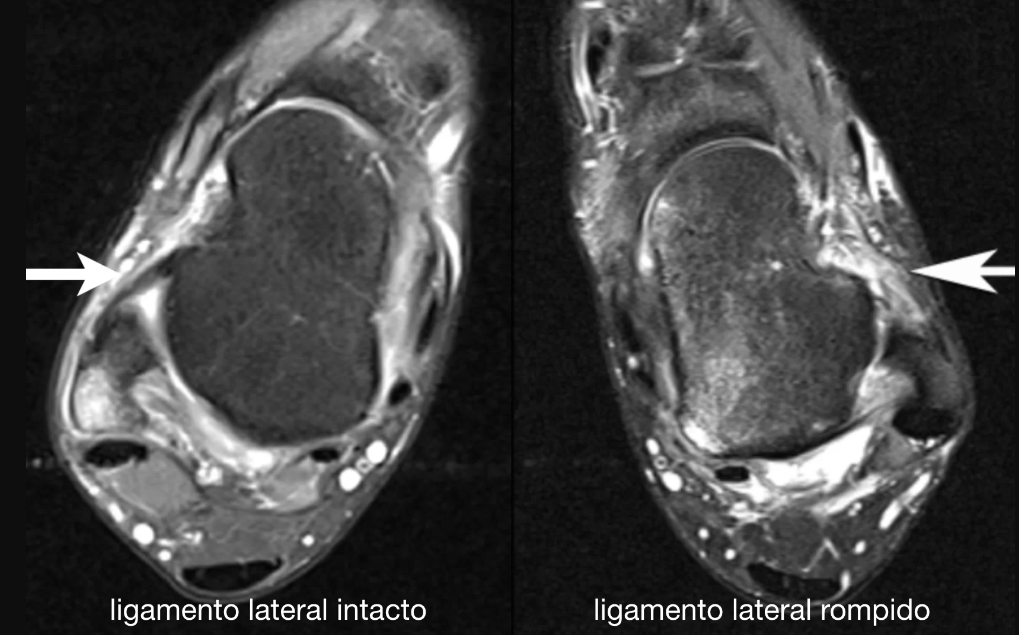

• Quais as principais características e indicações para a solicitação da ressonância magnética?

A

• Diferenciar camada superficial e profunda

• Bom para atletas competitivos

• Não invasivo

• Corte axialtalofibular anterior e posterior, camadas profundas

• Corte coronalcalcaneofibular, deltóide